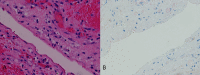

Figure 5

Microscopic aspect of the lesion. (A) The cyst was lined with a single layer of flat cells, without atypia. Underlying this layer was a dense collagenous fibrous tissue and a thin band of inflammatory cells, mostly histiocytic cells (H&E 400×). (B) Mesothelium origin of the cells covering the cyst was confirmed by negative immunostaining with BerEp4 (BerEp4 400×).